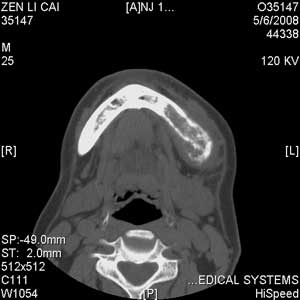

以下是引用jiangjing在2008-5-28 15:56:00的发言:[br]下颌骨左侧部骨质破坏,轻度膨胀,瘤骨形成,软组织肿胀考虑 恶性骨肿瘤-----肉瘤类